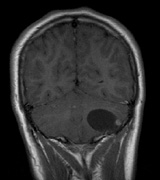

CNS hemangiomas are the most common tumor of VHL, affecting 60% to 80%, with a predilection for the cerebellum and spinal chord. An enlarging cystic component is a frequent finding in symptomatic tumors. Patients typically present in their early 30s; headaches or neck pain in affected individuals should not be ignored.172,173 On microscopy, CNS hemangiomas resemble retinal capillary hemangiomas. Their malignant potential is low.174 The treatment is surgical (Fig. 17, A and B).13

Fig. 17. Images from a 13-year-old boy with Von Hippel-Lindau syndrome. (a) Coronal postcontrast T1-weighted imaging reveals a cystic lesion with an enhancing nodule at the pial surface typical of a hemangioblastoma. (b) A second solid enhancing hemangioblastoma is seen at the craniocervial junction on a sagittal postcontrast T1-weighted image. (c) Associated cystic lesions (arrows) are seen within the pancreas.

Pancreatic lesions may be nonsecretory (most commonly cysts or cystadenomas) or secretory (islet cell tumor).179 In one study of 52 patients, 56% (29 patients) were found to have pancreatic lesions. The majority (19 of 29) had cystic changes only (Fig. 17C). Pancreatic lesions were the only abdominal manifestation of disease in 6 of 52 patients.180 In a separate study, pancreatic cysts did not show significant progression on follow-up examinations over an average period of 5 years.181 Like pancreatic cysts, islet cell tumors appear to be frequently asymptomatic.182